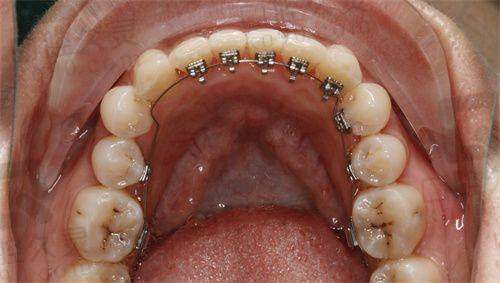

制定矫正方案是牙齿矫正过程中非常重要的一步。衢州蓝芽口腔医院的医生们会根据患者的牙齿情况、面部特征和个人需求等因素,制定出更适合患者的矫正方案。在我的矫正方案制定过程中,医生们进行了多次的讨论和分析。他们综合考虑了我的牙齿排列不齐的程度、咬合关系以及我的面部美观等因素,更终为我选择了隐形矫正的方案。隐形矫正具有美观、舒适、可自行摘戴等优点,非常适合我这种对美观要求较高的患者。医生还使用了精良的数字化模拟技术,为我模拟了矫正后的牙齿成效,让我提前看到了矫正后的自己。看到模拟成效后,我对矫正充满了信心。

衢州蓝芽口腔医院采用的隐形矫正技术是一种非常精良的牙齿矫正技术。这种技术使用的是透明的矫正器,几乎看不出佩戴的痕迹,不会影响到我的美观。而且,隐形矫正器可以自行摘戴,方便我在进食、刷牙和清洁口腔时取下,保持口腔卫生。与传统的金属矫正器相比,隐形矫正器更加舒适,不会对口腔黏膜造成刺激。此外,隐形矫正技术还可以通过数字化模拟技术,严谨地控制牙齿的移动,缩短矫正时间,提高矫正成效。在佩戴隐形矫正器的过程中,我几乎感觉不到任何不适,而且可以正常地进行日常生活和工作。